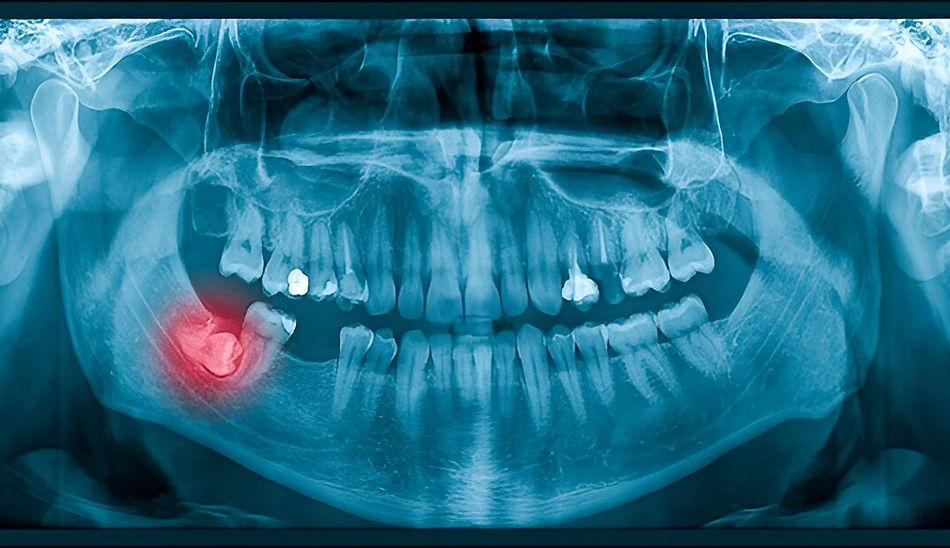

If your dentist notices these issues on an X-ray or exam, they may recommend wisdom teeth extraction—usually before problems become more serious.

Step 1: Consultation and Imaging

We start with a full evaluation, including digital X-rays, to assess the position and development of your wisdom teeth. This allows us to determine whether extraction is necessary and plan the safest, most efficient way forward.